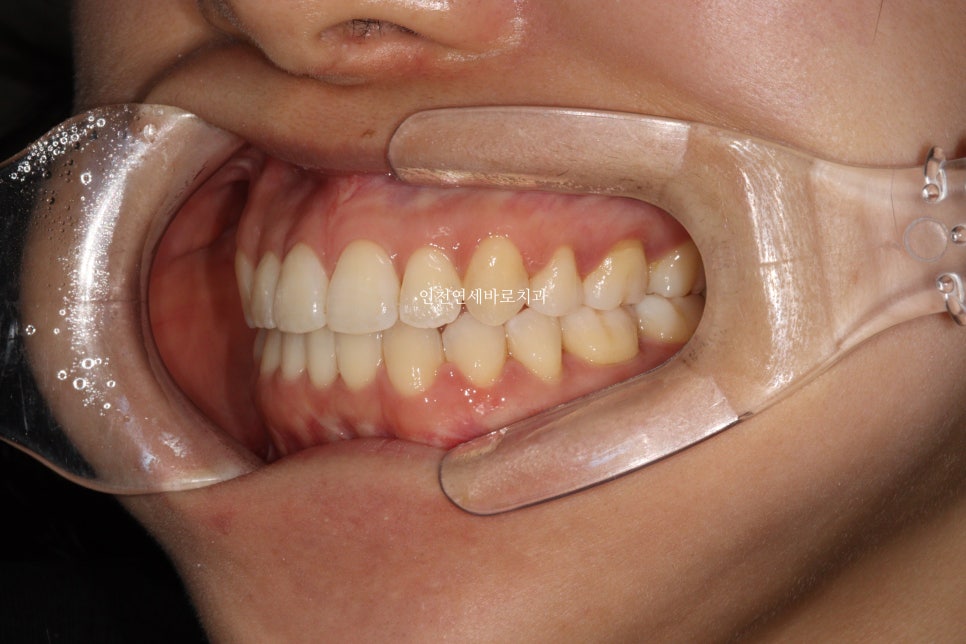

지난 주 마무리된 모습

결손치아가 있지만 교합은 문제없게 마무리

그리고 중요한 앞모습

과정이야 힘들고 오래걸리고 장치도 교체하고 어려웠지만

목표한바는 모두 달성한 치료입니다.